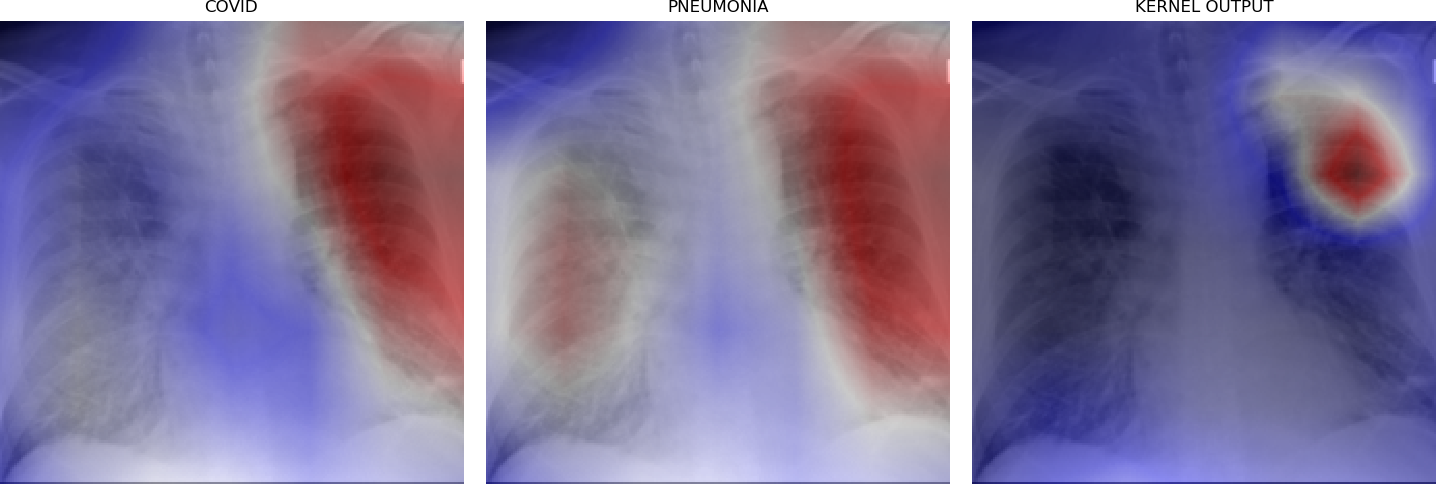

Figure 5 shows triples of X-ray images with superimposed class activation maps for predictions obtained from expert binary models (images one and two) with the third image showing the heat maps computed using our kernel. The intended use of our method is to examine positive classifications from two possibly overlapping classes (i.e. COVID-19, Pneumonia) and extract discriminative features pertaining to the class of interest, i.e. COVID-19. Triples (a)-(f) show positive classifications of COVID-19 and Pneumonia by their respective binary expert models along with class activation maps that localize the image region responsible for that classification. The third image in each triple shows a better localized image region for COVID-19 as computed using our method. Our method is intended to improve explainability of predictions under circumstances where both models return positive classifications resulting in significant overlap in activation maps.

Figure 6 demonstrates the role of the kernel parameter . It controls amplification of the directed differences among the activation maps. Higher values of concentrate the resulting heat map to a smaller region.